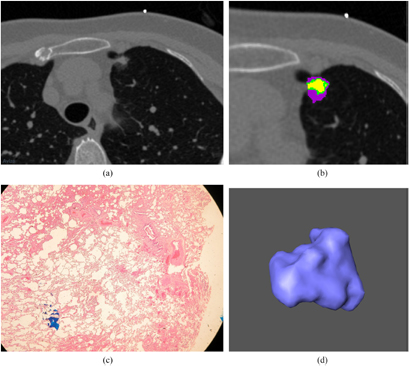

An open software package Imaging Biomarker Explorer (IBEX) was used in the nodule delineation and quantitative analysis of radiomics feature extraction from the thin-section CT images (Zhang et al 2015). Radiomics is an emerging research area in medical imaging for advanced image analysis in which quantitative features of tumor phenotypes are extracted from an imaging modality such as computed tomography, magnetic resonance imaging, or positron emission tomography (Kumar et al 2012, Lambin et al 2012, Aerts et al 2014, Zhang et al 2015). These phenotypic features include tumor shape, statistical distribution of gray-scale intensities, and texture properties (Kumar et al 2012, Lambin et al 2012, Aerts et al 2014, Zhang et al 2015). In our work using localized thin-section CT with radiomics feature extraction and machine learning, nodules were first manually delineated by an experienced research assistant on the image viewer of IBEX. Final nodule delineation was modified and approved by a radiologist whose expertise is in the lung cancer imaging. Two sets of images of a benign and malignant nodule acquired from the localized thin-section CT scan are shown in figures 2 and 3. Their corresponding pathological photographs and 3D views are also shown.

Standard image High-resolution imageFigure 3. (a) A malignant nodule is shown in a localized thin-section CT image. The window level is −500 HU and the window width is 1500 HU. A 60-year-old female has a speculated and malignant nodule in LUL. (b) An enlarged image of figure 3(a). Different subregions within the benign nodule are identified by clustering pixels based on different CT densities. (c) A pathological photograph of this malignant nodule is shown in figure 3(a). The microscopic view of the cellular scale is shown. (d) A 3D view of this malignant nodule is shown in figure 3(a). The morphological view is shown by the computer graphic method of surface rendering.